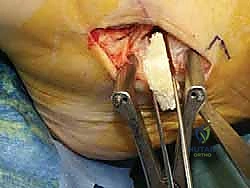

الخطوة الرابعة: تقييم وإصلاح رباط الدالية (Repair vs. Reconstruction)

بمجرد الوصول إلى رباط الدالية، يتم تقييم درجة التلف:

* الإصلاح المباشر (Direct Repair): إذا كانت أنسجة الرباط الممزقة ذات جودة جيدة (عادة في الإصابات الحديثة)، يقوم الدكتور هطيف بخياطتها مباشرة. يستخدم خطاطيف تثبيت عظمية (Suture Anchors) صغيرة جداً ومصنوعة من مواد متوافقة حيوياً (تذوب مع الوقت أو من التيتانيوم) لغرس الخيوط القوية في عظمة الكعب الإنسي، ثم يتم سحب الرباط الممزق وتثبيته بقوة في مكانه التشريحي الأصلي.

- إعادة البناء (Reconstruction): في الحالات المزمنة حيث يكون الرباط الأصلي قد تليف، تآكل، أو أصبح غير كافٍ للاستخدام، يلجأ الدكتور هطيف إلى تقنية "إعادة البناء". تتضمن هذه التقنية المتقدمة استخدام رقعة وترية (Graft)، إما من جسم المريض نفسه (Autograft - مثل أوتار الركبة أو وتر من القدم) أو رقعة صناعية متطورة. يتم حفر أنفاق ع